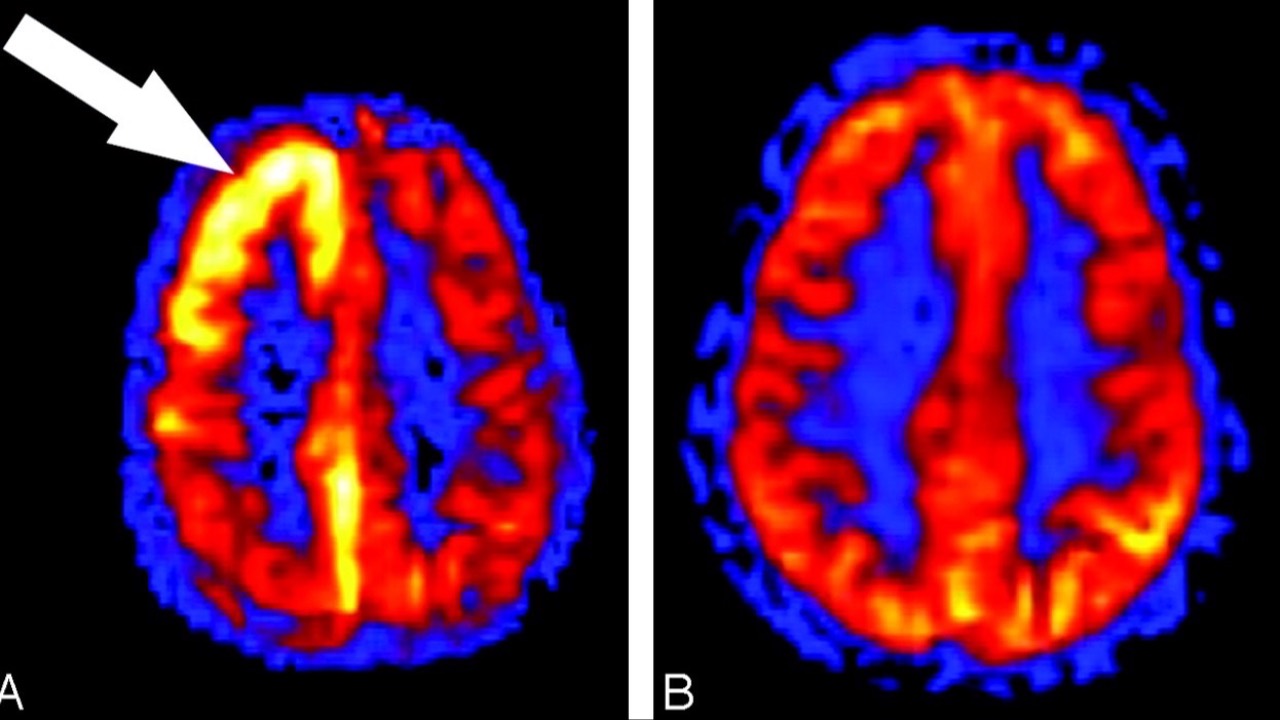

Brain Atrophy & AMD

Could this be a new biomarker?...

An article published in the American Journal of Ophthalmology last week reveals a significant association between outer retinal thinning and brain atrophy in early age-related macular degeneration (AMD). This correlation, particularly strong in vision-related b...